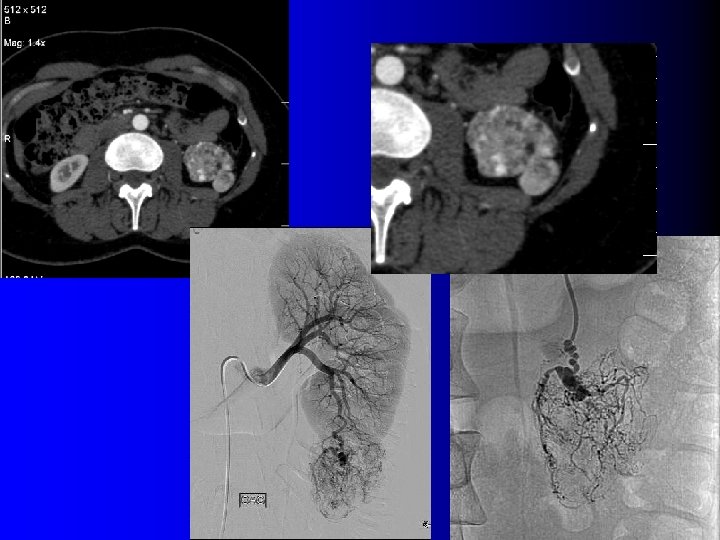

Tomodensitométrie Tumeur hypervasculaire avec plages de densité graisseuse (-10 UH à -100 UH) l l Intérêt : – Diagnostique – Thérapeutique : l Taille exacte l Localisation l Importance du contingent vasculaire l Technique d'examen rigoureuse: – Minimiser les effets de volume partiel l Coupes fines (millimétriques) l Examen sans injection

Tomodensitométrie Tumeur hypervasculaire avec plages de densité graisseuse (-10 UH à -100 UH) l l Intérêt : – Diagnostique – Thérapeutique : l Taille exacte l Localisation l Importance du contingent vasculaire l Technique d'examen rigoureuse: – Minimiser les effets de volume partiel l Coupes fines (millimétriques) l Examen sans injection

TDM: cas des AML très vasculaires l Très nombreux vaisseaux dysmorphiques – Washout précoce – Diagnostic: l l Contexte (STB, LAM) Micro-anévrysmes visibles en TDM

TDM: cas des AML très vasculaires l Très nombreux vaisseaux dysmorphiques – Washout précoce – Diagnostic: l l Contexte (STB, LAM) Micro-anévrysmes visibles en TDM